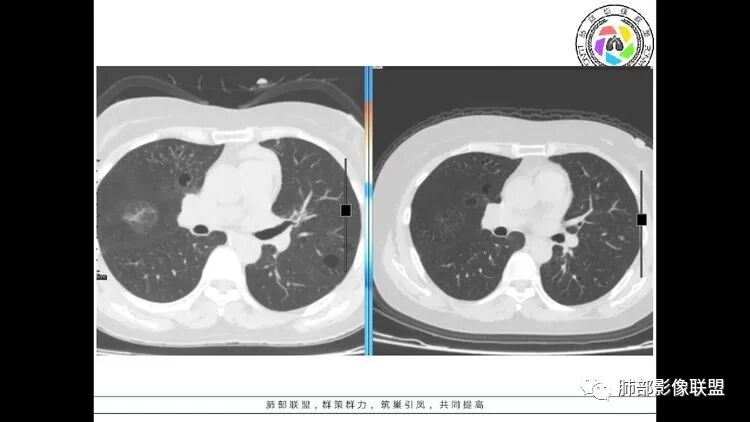

老年女性,眼炎入院,血常规正常,双肺多发囊状影,病变随机分布,形态单一,与血管关系密切,考虑LIP。左下肺混合GGO,边界尚清,贴近囊腔,鉴别腺癌。炎症指标无异常暂不考虑感染性病变。

胸CT:1.双肺多发囊性变,以中下肺为主,病变边缘可见肺动脉,部分囊内可见分隔及肺动脉,双下部分肺野周围可见小叶中心结节及树丫征。

2 左肺上叶尖后段 右肺上叶前段 右肺下叶外基底段 结节影,边界清楚,可见柔软毛刺,左肺下叶后基底段混合密度影。

3.纵隔淋巴结肿大?,以主动脉弓为界向上向下增大。

考虑:淋巴瘤肺浸润,眼部症状考虑与此有关;LIP?;继续鉴别肺腺癌?血管炎?。

双肺多发磨玻璃结节,其内可见空腔,周围边界清晰,多发囊,左肺实性结节。考虑间质性肺炎,LIP可能性大。鉴别腺癌。

患者中年女性,因右眼红痛1天就诊。胸CT:双肺多发囊性变及结节影,囊以中下肺为多,部分囊内可见分隔及肺动脉,结节部分为实性,部分为混合性,边缘光滑,未见明显毛刺、棘突、胸膜牵拉及血管集束征象。双中下可见支气管扩张及树丫征。淋巴结无明显肿大。综合考虑:一元淋巴细胞间质性肺炎。多元鉴别肺腺癌并转移等恶性病变。

中年女性,双肺多发囊性变,以中下肺为主,病变边缘可见肺动脉,部分囊内可见分隔及肺动脉,左肺上叶较大结节,可见分叶、月牙铲,左肺下叶、右肺中叶磨玻璃病灶,边界清楚,内有空泡,结节,可见尖后段 右肺上叶前段 右肺下叶外基底段 结节影,边界清楚,纵隔淋巴结肿大,

考虑腺癌,淋巴管肌瘤病?LIP?